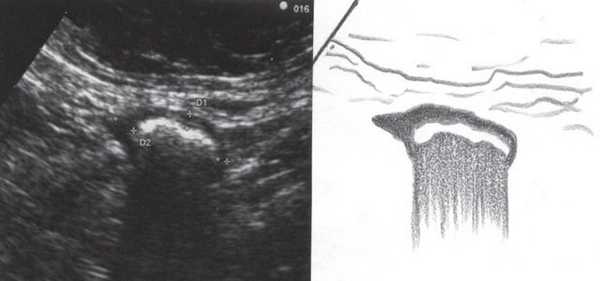

При УЗИ были выявлены диффузные изменения печени и поджелудочной железы, признаки хронического бескаменного холецистита, ангиомиолипома левой почки (без динамики за несколько лет), состояние после экстирпации матки с придатками. В левой подвздошной области соответственно зоне максимальной пальпаторной болезненности на протяжении 9 см отмечалось утолщение стенок толстой кишки до 6-7 мм (рис. 1). Перистальтика кишки отсутствовала, гаустрация была слабо выражена, при этом визуализировалось несколько болезненных при надавливании датчиком выпячиваний пониженной эхогенности, размером от 7 до 20 мм (рис. 2, а, б) с тонкой стенкой до 0,9-1,1 мм и наличием в некоторых из них фрагментов кишечного содержимого и газа (рис. 3, а, б).

Рис. 2. Эхографическая картина дивертикулита. Трансабдоминальное исследование линейным датчиком 7,5 МГц.

а) Продольный срез.

б) Поперечный срез.